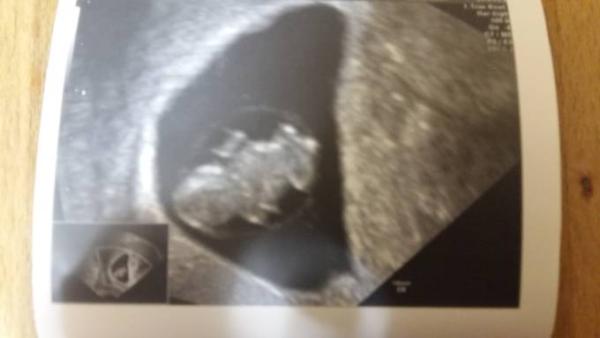

Hallo, danke nochmal für das Daumen drücken es hat geholfen Mein kleiner Astronaut ist 1,6 cm und das Herz schlägt mit 150 die Minute..bis jetzt sieht alles gut aus..Bild hängt an..Liebe Grüße, Naddel.

Bild zu Zurück vom FA Termin - Forum für Juli - Mamis